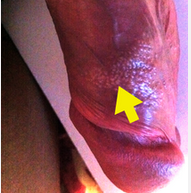

龜頭上有小顆粒?龜頭上面或龜頭周圍出現(xiàn)小顆粒,要警惕炎癥及性病,最好是盡快到醫(yī)院做個檢查,找準原因,盡早治療。專家將教您如何區(qū)別龜頭上長顆粒是炎癥還是性病,詳細如下:

① 包皮龜頭炎具有龜頭長小顆粒的癥狀,包皮龜頭炎又分為包皮炎和龜頭炎,由于常常同時出現(xiàn)故稱為陰莖包皮龜頭炎。這種炎癥可以是感染性的和非感染性的,臨床上以感染性的包皮龜頭炎較多見,患者可明顯感覺到包皮或龜頭瘙癢,有的伴有灼痛感,且龜頭有異味。龜頭炎種類較多,臨床癥狀表現(xiàn)也多種不一。

② 性病也可出現(xiàn)龜頭長顆粒的現(xiàn)象:如尖銳濕疣、淋病、生殖器皰疹等性病,往往有龜頭出現(xiàn)小顆粒的現(xiàn)象。患者多有不潔性生活,當然,也可能是妻子患有傳染性的炎癥誘發(fā)。另外,包皮垢刺激等非感染因素,也可誘發(fā)性傳播疾病。